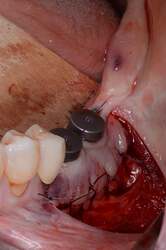

Fig. 3.

Alveolar ridge augmentation of the posterior maxilla. A Initial intraoperative situation with an extended alveolar defect of the posterior alveolar jaw. B Intraoperative situation after sinus floor elevation and fixation of two allogeneic cortical bone plates buccal and palatinal using four fixation screws. C Intraoperative situation after filling sinus floor with xenogeneic bone substitute, covering it with PTFE matrix and filling the alveolar crest with allogeneic spongious granules. D After 4 months, sufficient bone remodeling, screws removed, and implants inserted. E Overlining with xenogeneic granules for resorption protection and covered by collagen matrix. F X-ray demonstrating inserted implants.